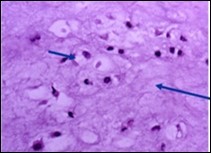

Figure 4.Enchondroma depicting lobules of hyaline cartilage with vacuolated cells and eccentric nuclei 12.

Enchondroma depicting            lobules of hyaline cartilage with             vacuolated cells and eccentric nuclei 12.